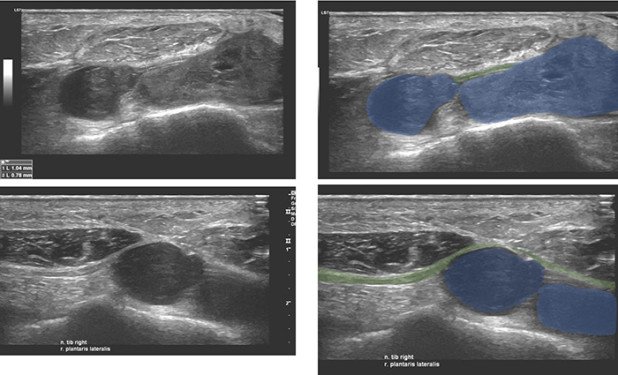

Die hochauflösende Nerven- und Weichteil-Ultraschalluntersuchung zeigt hingegen eine Raumforderung im Bereiche des Innenknöchels mit Proximität zum Nervus tibialis (Abb. 1).

- Sonographie: Raumforderung im Innenknöchelbereich, DD Nervenscheidentumor